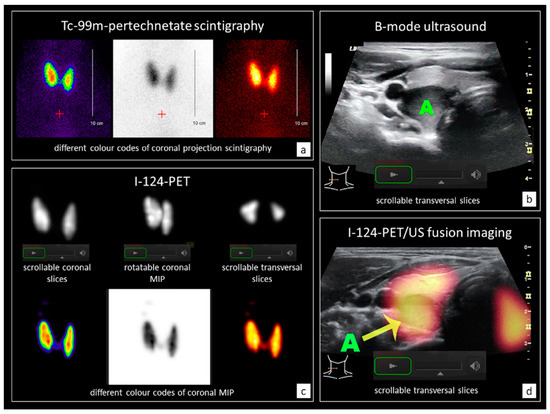

2.2. Conventional Diagnostics (CD) and I-124-PET/US Fusion Imaging (PET/US)